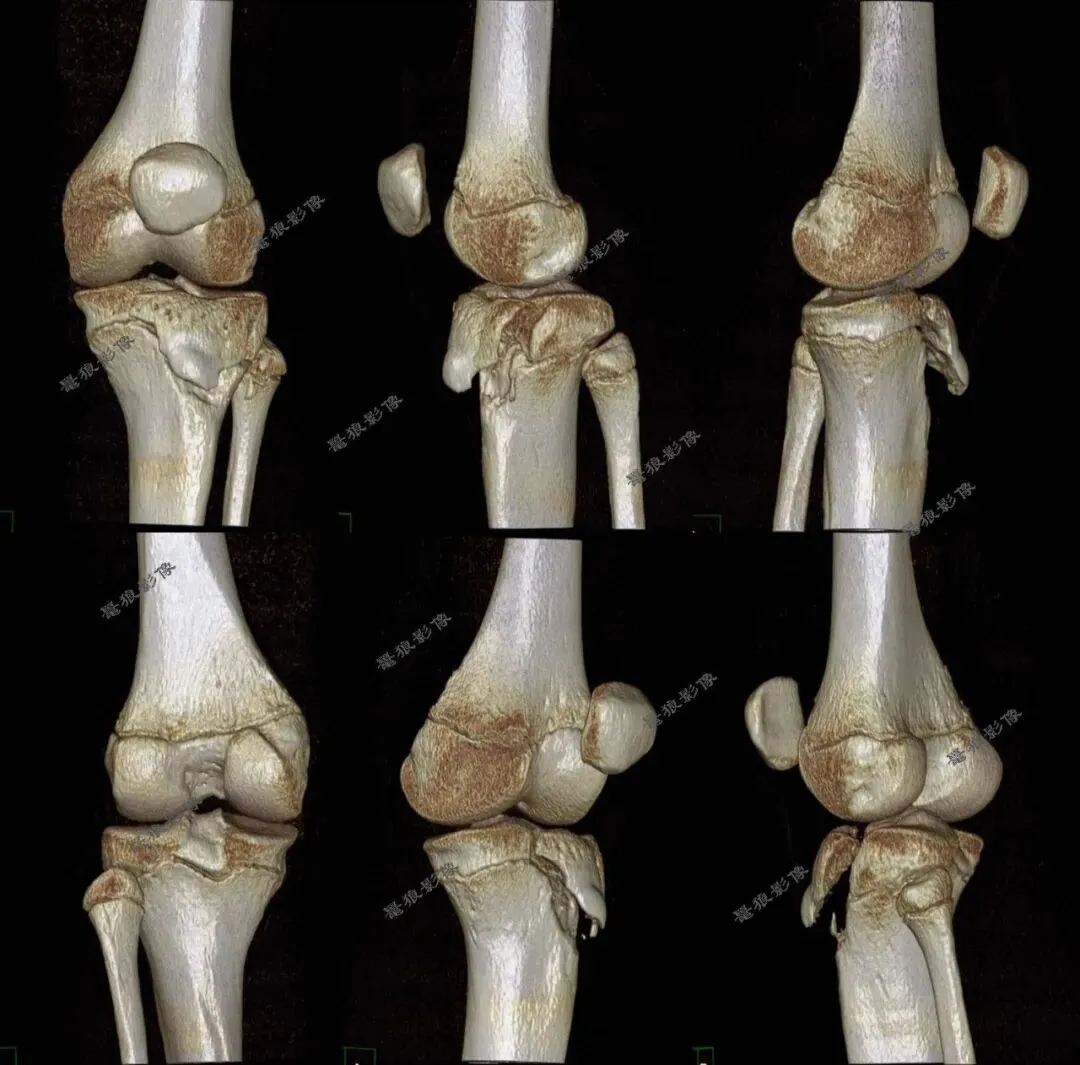

D、胫骨结节骨折病例分享

M,11y。

缘患者入院3小时余前运动后出现左膝部疼痛,活动受限,当时无昏迷,遂送至急诊就诊,查X片:左胫骨结节骺离骨折。

一.术前X线片

二.术前CT

胫骨结节骨折(OgdenIIIA型 )